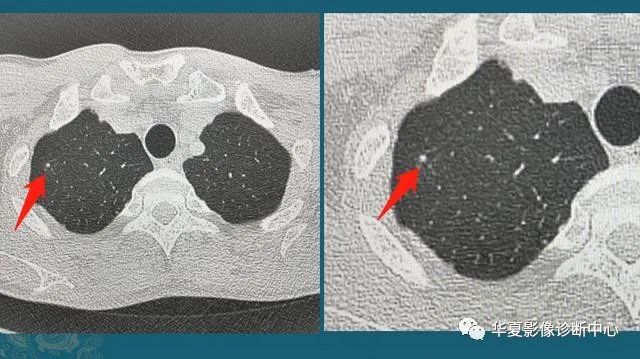

下图是两位女士,左图是当年在萤石矿上打工,当时条件简陋防护不到位,长期吸入粉尘,在肺里形成很多小结节:

图3

右图是一位采棉女工,长期吸入植物性粉尘,在肺里形成很多微结节和索条状影。

类似的尘肺病包括13种,包括矽肺、煤工尘肺、焊工尘肺等。既往尘肺分为致纤维性尘肺(危害大)和非致纤维性尘肺,矽肺、石棉肺、滑石尘肺为致纤维性尘肺;而吸入某些金属粉尘(如铁、钼),在肺组织内呈现一般的异物反应,脱离粉尘后可以逐渐减弱,对人体危害较小。